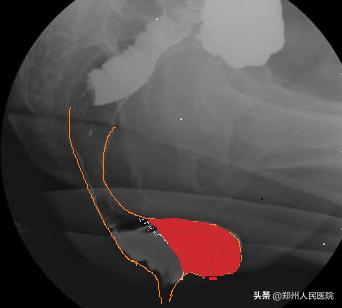

肛肠外科副主任张胜威了解情况后,他怀疑杨大妈患的不是普通的便秘。通过肛门指诊和直肠排粪造影,确定了杨大妈患的是 直肠前突型便秘 。经过 便秘MDT诊疗团队 会诊,由妇科和肛肠外科同时为杨大妈进行了阴道后壁修补术和直肠前突修补术,一次解决了两个问题。

咱们说的 直肠前突型便秘 ,作为出口梗阻型便秘的一种,又称直肠前膨出,多发生于中老年女性。 直肠前突 即直肠前壁突出,是直肠阴道隔薄弱直肠前壁突入阴道内的一种病理状态,是排便困难的主要因素之一。咱先来看看直肠的正常状态

再看看这个

这突出的地方像不像个鹅头这种影像学改变在临床上我们称之为 “鹅颈征” 是直肠前突型便秘的典型症状

妈呀看到这些小编不禁汗毛竖立如果您有这些症状,下一步就要来检查了 一般来说,医生在详细问询病史后,通常至少要做2个检查才能进一步确诊, 肛门指诊 和 排粪造影 。